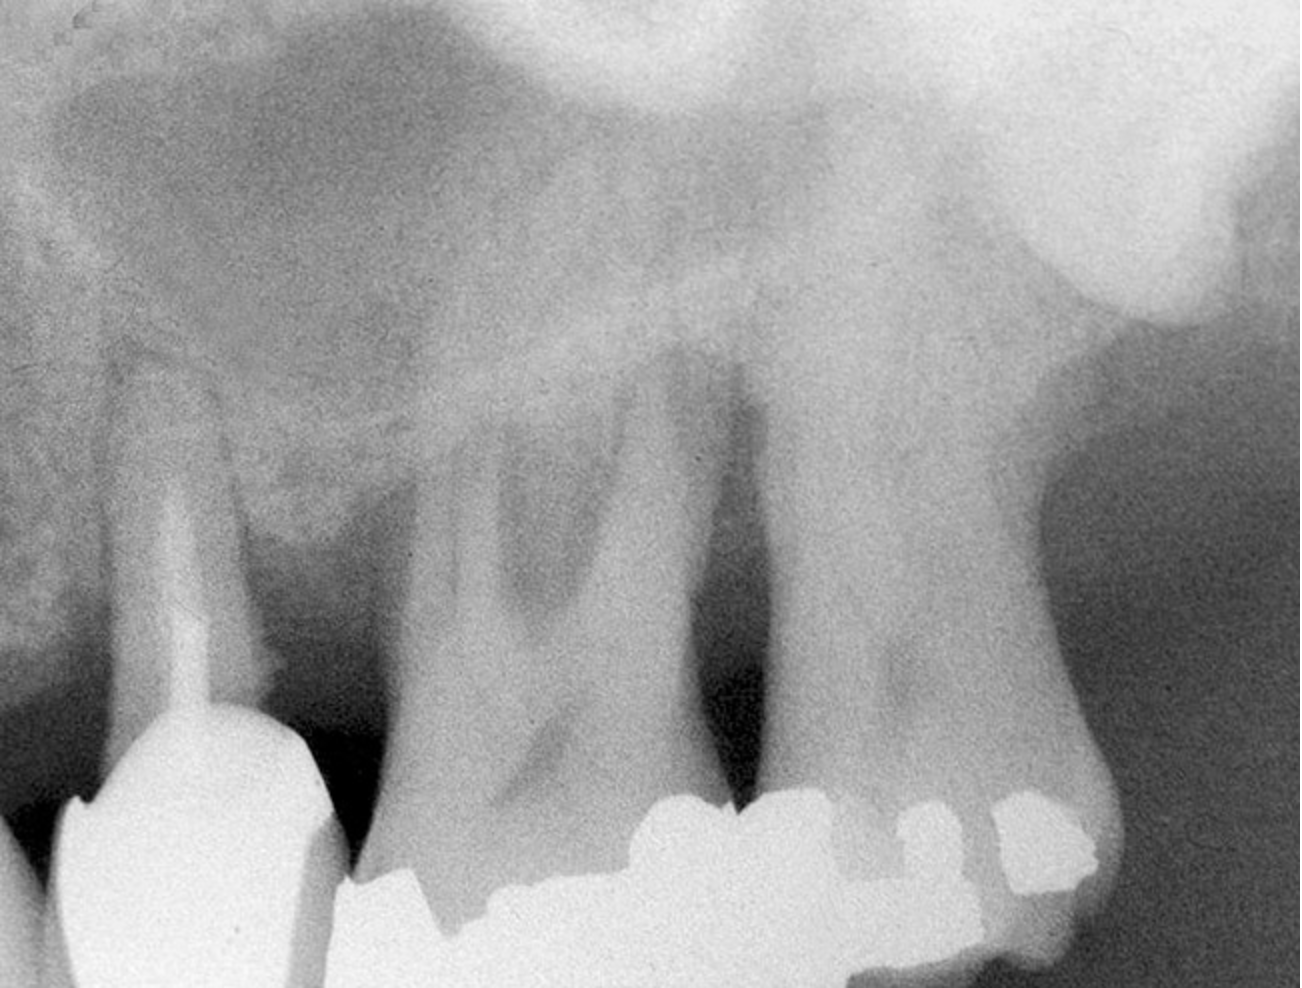

First, a periapical radiograph is taken to determine the amount of bone subantrally. It should be noted that a periapical film has an average error of 14%.23 Therefore, it is advantageous to take the radiograph in a manner that includes a marker (5-mm wide ball bearing) in order to be able to calculate the magnitude of radiographic error (Figure 1).

Figure 1  At tooth site No. 14, a periapical radiograph was taken with the long-cone paralleling technique. The radiographic ball marker measured 5.8 mm while its actual diameter is 5 mm. The enlargement is 0.8 mm, therefore the magnification error is 0.8/5 = 16%. By correcting for this error, a closer approximation of the amount of bone from the osseous crest to the sinus floor can be made.

Figure 1